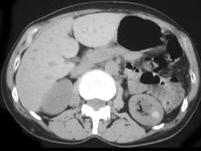

问题 女,28岁,请根据所示图像,选择最可能诊断 ( )

选项 A、左侧高密度肾囊肿 B、左侧单纯性肾囊肿合并感染 C、左侧单纯性肾囊肿 D、左侧钙化性肾囊肿 E、左侧肾癌

答案 A